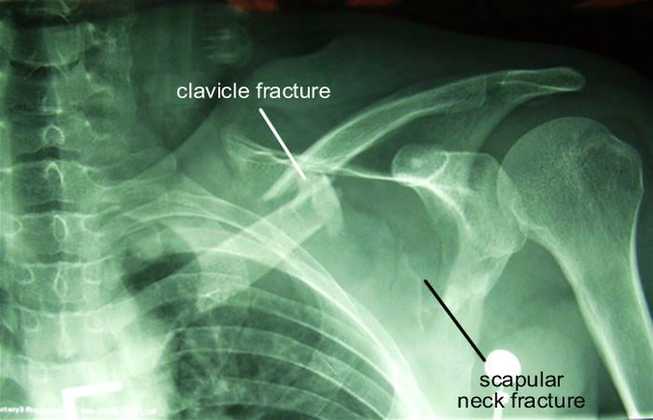

Рентген плеча: примеры снимков и их расшифровка